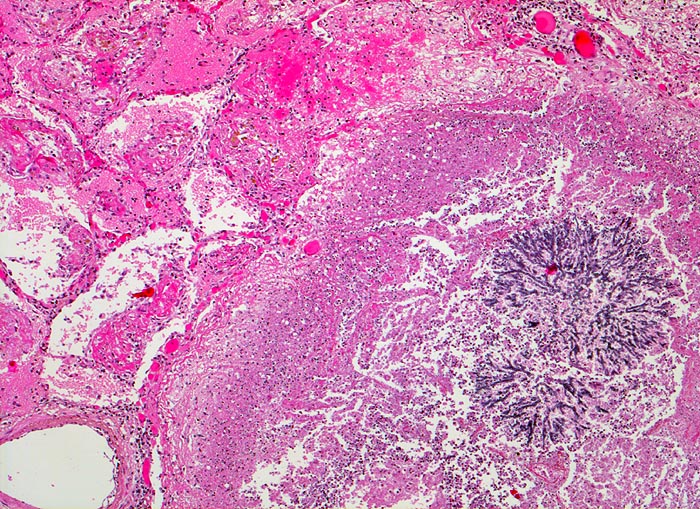

Aspergilluspneumonie

Lunge

Herd mit zentraler Einschmelzung (nekrotischer Detritus und zerfallende Granulozyten). Im Zentrum der Nekrose verzweigtes Aspergillusmycel. Die Kapillaren der angrenzenden Alveolen sind hyperämisch. In den Alveolarlichtungen sind Fibrinexsudate nachweisbar.

Seit 14 Monaten bekannte chronische lymphatische Leukämie behandelt mit Chemotherapie. Der Patient entwickelt unter Therapie eine Pneumonie und verstirbt an einer Pilzsepsis.

Es handelt sich im vorliegenden Fall um eine akute fibrinöse Entzündungsreaktion. Chronische Aspergilluspneumonien kommen ebenfalls vor.

Histologie

50